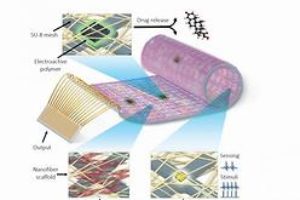

An alternative to heart transplantation could one day be in the cards for patients with heart failure; scientists have created a “bionic heart patch” that allows doctors to remotely …